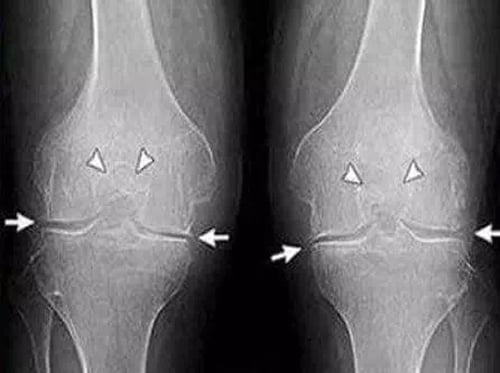

Болезни суставов нельзя игнорировать — они развиваются иногда незаметно, но их последствия бывают очень тяжёлыми. К сожалению, в России с подобными проблемами сталкивается каждый пятый человек, а после 50 лет — уже каждый третий. И это не просто цифры: за ними скрываются годы боли, ограниченная подвижность и риск инвалидности.

Я как специалист-ревматолог каждый день вижу пациентов, которые долго терпели и занимались самолечением. Итог всегда один: болезнь прогрессирует, суставы разрушаются, и вернуть их в норму становится намного сложнее.

Поэтому важно вовремя обратить внимание на тревожные симптомы — боль, хруст, скованность движений. Суставы нужно лечить сразу, а не тогда, когда человек уже не может встать с кровати. Чем раньше начата терапия, тем больше шансов сохранить активность и полноценную жизнь на долгие годы.